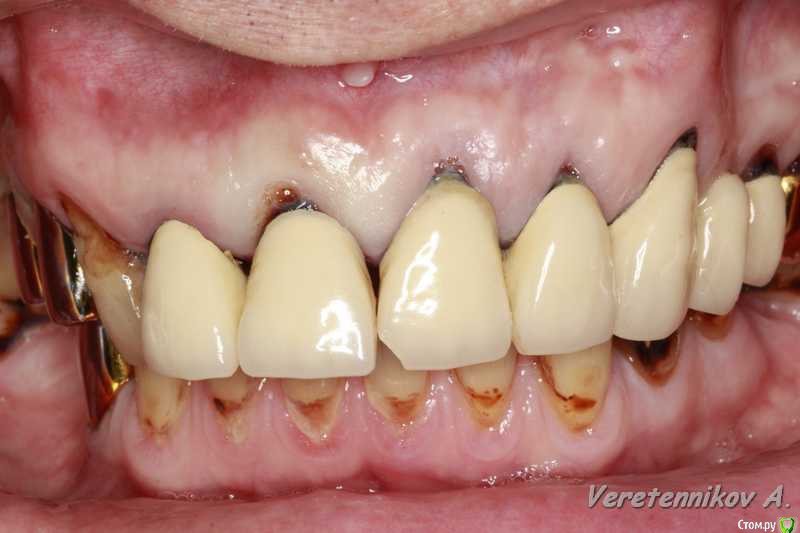

an_ver Опубликовано 26 марта, 2015 Поделиться Опубликовано 26 марта, 2015 (изменено) 11,12..11 трещина корня,вест.часть,12 рыхло все..сгнило.Убрал,кюретаж,11 вест. стенки нет на 2/3.Установил 11-4,2*13;12-3,75*13 мм..все Альфа.Мп3,мембрана эволюшн.11 заглушил,12-временный абатмент,коронка.Шил викрил 4,0. Фсе...пинайте Изменено 26 марта, 2015 пользователем an_ver 7 Ссылка на комментарий

M@estro Опубликовано 26 марта, 2015 Поделиться Опубликовано 26 марта, 2015 Андрей, все вроде ок , смущает два вопроса навскидку. 1) непосредственная нагрузка консолью . Я бы так не рисковал .2) этап планирования. В таких кейсах я предпочитаю все демонтировать - и оценить состояние зубов, и уже после этого планировать удаления / имплантацию. Объясни, почему так поступил? 5 Ссылка на комментарий

an_ver Опубликовано 27 марта, 2015 Автор Поделиться Опубликовано 27 марта, 2015 Андрей, все вроде ок , смущает два вопроса навскидку. 1) непосредственная нагрузка консолью . Я бы так не рисковал .2) этап планирования. В таких кейсах я предпочитаю все демонтировать - и оценить состояние зубов, и уже после этого планировать удаления / имплантацию. Объясни, почему так поступил? Андрей, все вроде ок , смущает два вопроса навскидку. 1) непосредственная нагрузка консолью . Я бы так не рисковал .2) этап планирования. В таких кейсах я предпочитаю все демонтировать - и оценить состояние зубов, и уже после этого планировать удаления / имплантацию. Объясни, почему так поступил? 1.На 11 вестибулярно нет на 2/3 высоты.Засыпал мр3+мембрана..чет очкуя я на такие грузить((. Предлагаем ему все снять,и если что времянки поставить..отказался на публике часто))) мало ли что))).но ничего швы сниму и это тоже сдерну Ссылка на комментарий

zubovnet Опубликовано 28 марта, 2015 Поделиться Опубликовано 28 марта, 2015 (изменено) Понравилось. Смело. Но меня тоже консоль смущает...... Я бы не рискнул ТАК нагружать.вообще консоль на имплантанте это разве норм? Каппу бы ему сделали прозрачную, а там где удалились зубы- пластмасски беленькой. И раскручивайте на снятие соседей- там, видать , тоже все печально Изменено 28 марта, 2015 пользователем zubovnet 1 Ссылка на комментарий

an_ver Опубликовано 29 марта, 2015 Автор Поделиться Опубликовано 29 марта, 2015 Понравилось. Смело. Но меня тоже консоль смущает...... Я бы не рискнул ТАК нагружать.вообще консоль на имплантанте это разве норм? Каппу бы ему сделали прозрачную, а там где удалились зубы- пластмасски беленькой. И раскручивайте на снятие соседей- там, видать , тоже все печальноДа тут раскручивать не надо,сам он все понимает.Каппу предлагал.Счас все устаканиться,швы сниму и дальше пойдем Ссылка на комментарий